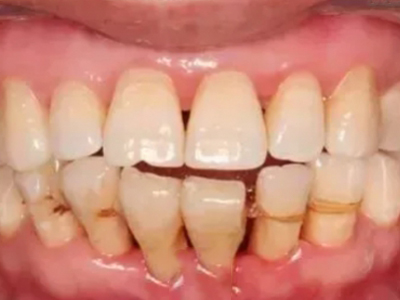

牙龈退缩多处牙龈萎缩出血图

牙龈退缩严重时,上排牙有多颗牙齿的牙龈部位发生退缩,导致牙根暴露,同时牙龈处还有出血的症状,伴有疼痛感,建议及时前往医院通过手术等手段进行治疗。